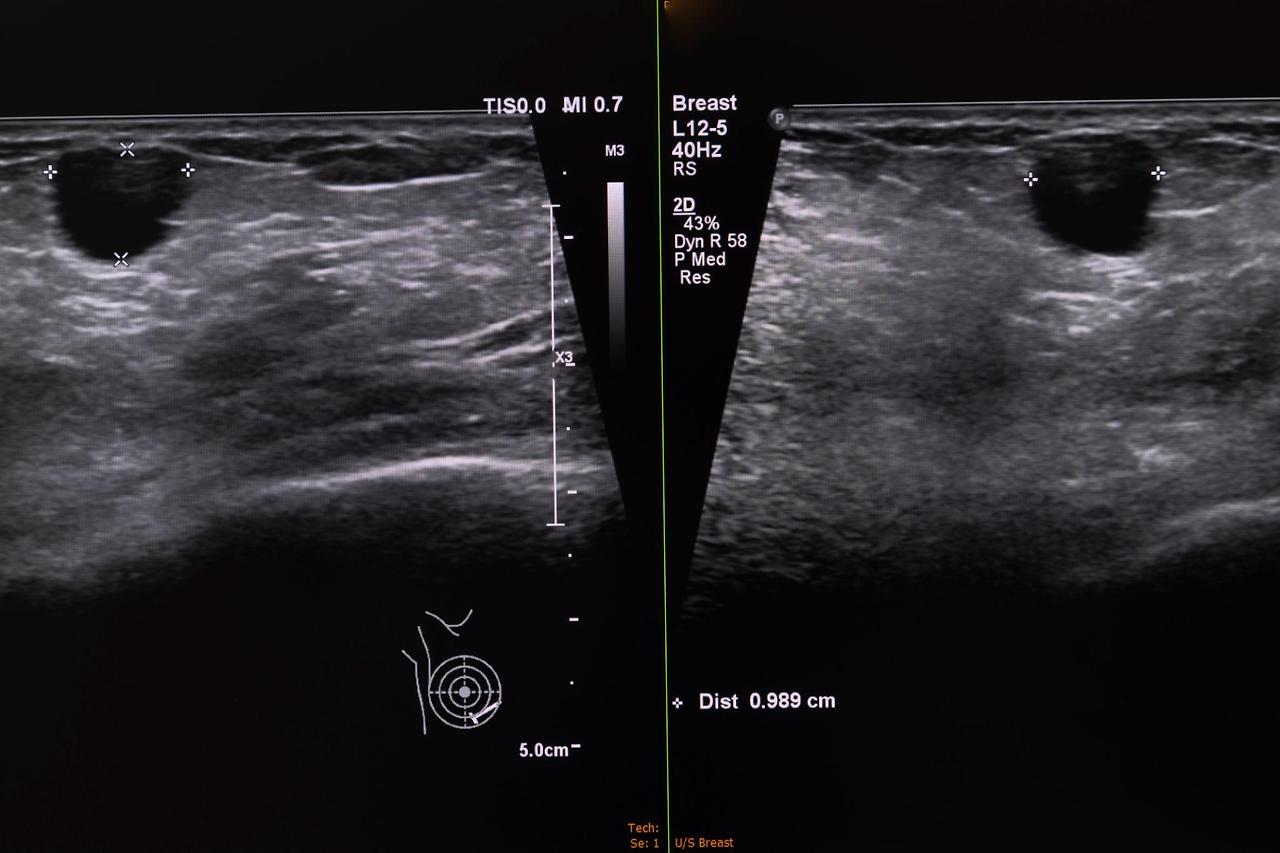

제가 검진 방법을 알아보면서 느낀 건, 유방 초음파와 유방 촬영술은 서로 보완 관계라는 점입니다. 유방 촬영술은 X-ray를 이용한 검사로, 미세 석회화(microcalcification)를 발견하는 데 유리합니다. 미세 석회화란 유방 조직 내에 칼슘이 침착되어 생긴 작은 점 같은 것으로, 초기 유방암의 신호일 수 있습니다. 반면 초음파는 종괴(mass)를 확인하는 데 강점이 있고, 특히 치밀 유방에서 숨어 있는 암을 찾아내는 데 효과적입니다.

40세 이상은 국가 검진으로 2년마다 유방 촬영술을 무료로 받을 수 있습니다(출처: 국민건강보험공단). 하지만 30대 여성이나 치밀 유방을 가진 경우에는 유방 촬영술로 암이 잘 보이지 않을 수 있어 초음파 검사를 병행하는 것이 좋습니다.